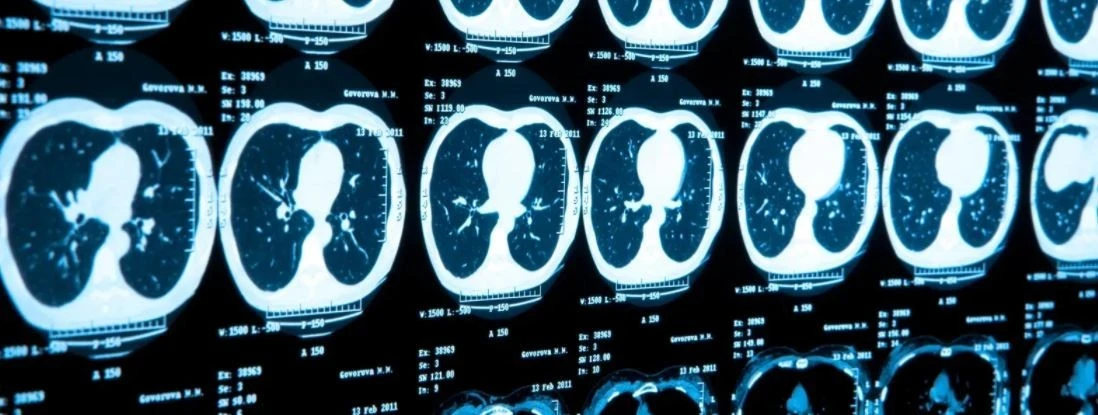

MRI, PET-CT, CT는 잘라낸 단면을 보여줍니다.

이런 면을 '슬라이스(slice)'라고 해요.

그리고 이런 사진들을 붙여서 3차원 이미지로 다시 만들 수도 있습니다.

저렇게 슬라이스로 잘라서 한 장씩 보는 셈입니다.

단면들을 모아서 다시 3차원으로 만들 수도 있어요.